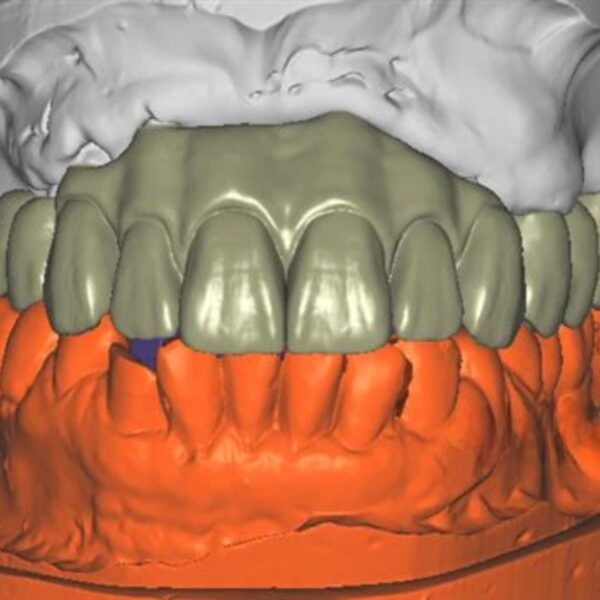

China Dental Design Complex Case Gallery

Challenging Projects That Showcase Our China Dental Design Expertise

Implant Crown Design

Advanced China Dental Design Capabilities

Our expert China Dental Design team delivers precision, quality, and cost-effectiveness for every complex restoration project